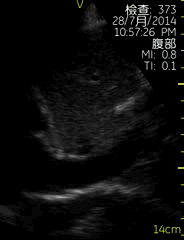

剑突下四腔切面

| 图像名称: | 剑突下四腔切面(二维) |

| 剑突下四腔切面(二维) |

| 心尖四腔切面(二维) | | 介绍重点: | 心脏各腔室大小正常、瓣膜运动协调;心包壁层脏层未见分离; |

| 心包壁层脏层分离,右心房/室前方可见液性暗区 |

| 左房/右房明显增大,右房后方可见明显心包液性暗区 | | 临床用途: | 心脏结构功能正常 |

| 心包积液 |